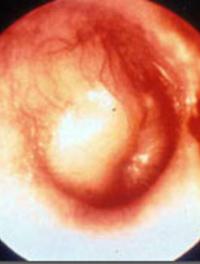

A l’âge de 5 ans, 5 à 8 enfants sur 10 présenteraient une otite séreuse. Les antibiotiques, décongestionnants ou corticoïdes par voie [...]

Jusqu’à l’apparition des antibiotiques, l’otite moyenne aiguë (OMA) de l’enfant était considérée comme une affection grave et les traités [...]

L’otite moyenne aiguë (OMA) est la cause la plus fréquente de prescriptions d’antibiotiques (AB) en pédiatrie. Le taux d’utilisation [...]

L’otite aiguë moyenne (OAM) est l’une des indications les plus fréquentes de l’antibiothérapie chez l’enfant. Chaque année, aux Etats-Unis, [...]